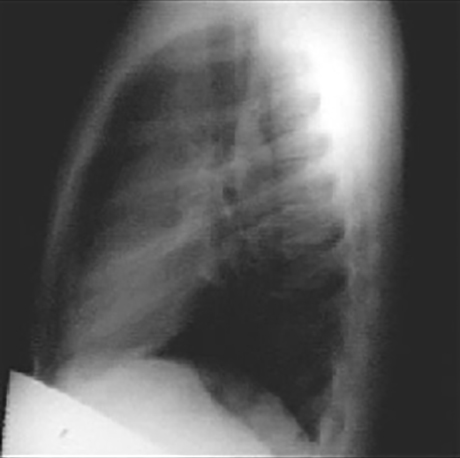

These chest X rays show a dilated ascending aorta.

The lateral view shows a dilated ascending aorta as evidenced by the shadow anterosuperior to the heart.